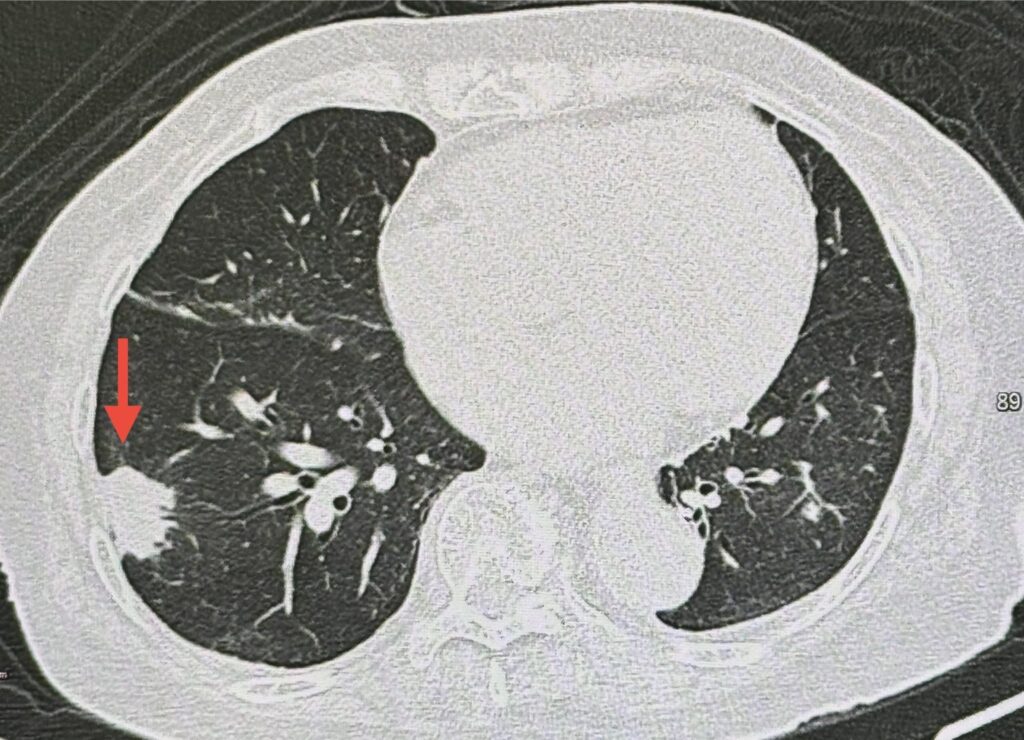

ตรวจร่างกาย ไม่มีไขั ฟังปอดปกติ เอกซเรย์ปอด มีเงาผิดปกติปอดข้างขวาด้านบนจากเคยป่วยเป็นวัณโรค และมีก้อนขนาด 1.9 x 1.9 เซนติเมตรที่ปอดข้างขวาด้านล่าง (ดูรูป) ก้อนนี้เป็นก้อนใหม่เพิ่งพบครั้งแรก ปีที่แล้วไม่มีก้อน ทำคอมพิวเตอร์ปอด พบก้อนขนาด 3.0 × 2.4 × 2.0 เซนติเมตรที่ปอดข้างขวาด้านล่าง ตรวจเลือด ค่ามะเร็งทุกตัวปกติ

เจาะก้อนด้วยเข็ม ส่งชิ้นเนื้อตรวจพยาธิวิทยา พบปอดอักเสบจากเชื้อราคริปโตค็อกคัส ตรวจเลือดหาคริปโตค็อกคัสแอนติเจนให้ผลบวก titer 1 : 20 ทำคอมพิวเตอร์สมอง และเจาะน้ำไขสันหลังปกติ ไม่พบเชื้อราคริปโตค็อกคัสกระจายเข้าเยื่อหุ้มสมอง

วินิจฉัย: ปอดอักเสบจากติดเชื้อราคริปโตค็อกคัส